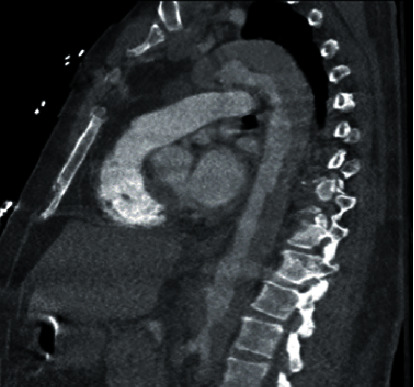

医源性主动脉夹层是经皮冠状动脉介入治疗(PCI)中一种罕见但可能致命的并发症。PCI术后的医源性主动脉夹层是罕见的,大多数病例报告夹层起源于冠状血管并扩散到升主动脉。本例剥离未累及冠状动脉,剥离从升主动脉延伸至降主动脉和髂血管。尽管经桡骨入路PCI的血管并发症比经股骨入路少,但仍可能发生明显的不良后果,需要及时干预。这个病例强调了高度不典型的医源性主动脉夹层在心导管置入后表现为急性肢体缺血。对于像我们这样的患者,由于整体预后不良,必须立即进行手术干预。

Iatrogenic aortic dissection is a rare but potentially fatal complication of percutaneous coronary intervention (PCI). Iatrogenic aortic dissection following PCI is rare with most cases reporting dissection originating within the coronary vessels with propagation into the ascending aorta. In this specific case, dissection was without coronary involvement, with dissection extending from the ascending aorta into the descending aorta and iliac vessels. Although PCI via radial approach is associated with fewer vascular complications than with femoral approach, significant adverse outcomes may still occur and require prompt intervention. This case highlights the highly atypical presentation of iatrogenic aortic dissection following cardiac catheterization presenting as acute limb ischemia. In such patients as with ours, immediate surgical intervention is necessary with overall poor prognosis.